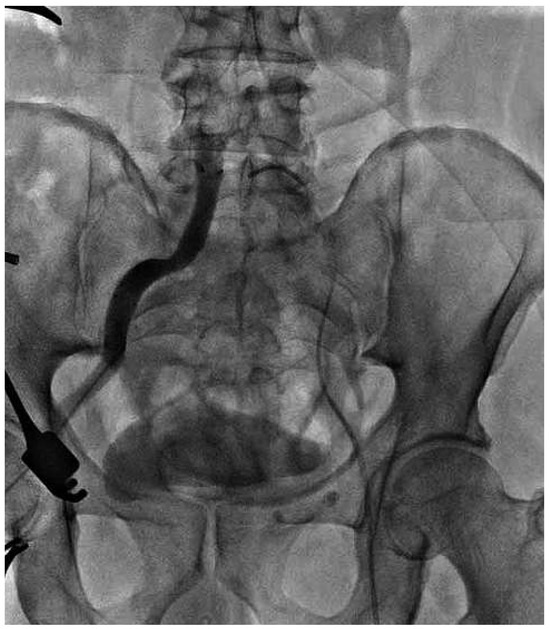

Endovascular Treatment of a Complex Type B Aortic Dissection

by Wen-Dong Li, Qing-You Meng, Li-Wei Zhu, Wen-Bin Wang, Ye-Qing Zhang, Cheng-Long Li and Xiao-Qiang Li

Cardiovasc. Med. 2013, 16(10), 267; https://doi.org/10.4414/cvm.2013.00187 - 23 Oct 2013

Aortic dissection is a rare disease with high morbidity and mortality, especially when involving multiorgan malperfusion such as lower extremity and visceral ischaemia. Revascularisation should be performed to restore perfusion immediately. We report a case of acute Stanford type B aortic dissection complicated [...] Read more.

Aortic dissection is a rare disease with high morbidity and mortality, especially when involving multiorgan malperfusion such as lower extremity and visceral ischaemia. Revascularisation should be performed to restore perfusion immediately. We report a case of acute Stanford type B aortic dissection complicated by lower extremity, renal and superior mesenteric ischaemia. The right iliac artery was occluded because of compression of the false lumen, resulting in thrombosis. The patient was successfully treated with endovascular treatments, including thrombus extraction and iliac artery, superior mesentic artery and aortic stenting combined with fenestration. Full article